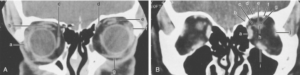

A CT scan of the orbits is a specialised imaging test that focuses on the eye sockets (orbits), surrounding soft tissues, eye muscles, optic nerves and adjacent bone structures. It provides much greater detail than a standard X-ray. This scan is typically recommended for:

Image Acquisition: The CT machine acquires thin sliced images of the orbits — both soft tissue and bones — which are then reconstructed for the radiologist’s review. The high-resolution CT scanner at the centre ensures good clarity of structures.